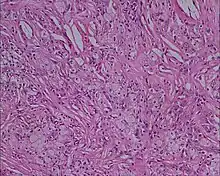

Xanthoma tuberosum

Xanthoma tuberosum (also known as tuberous xanthoma) is characterized by xanthomas located over tuberosity of the joints.[2]: 530